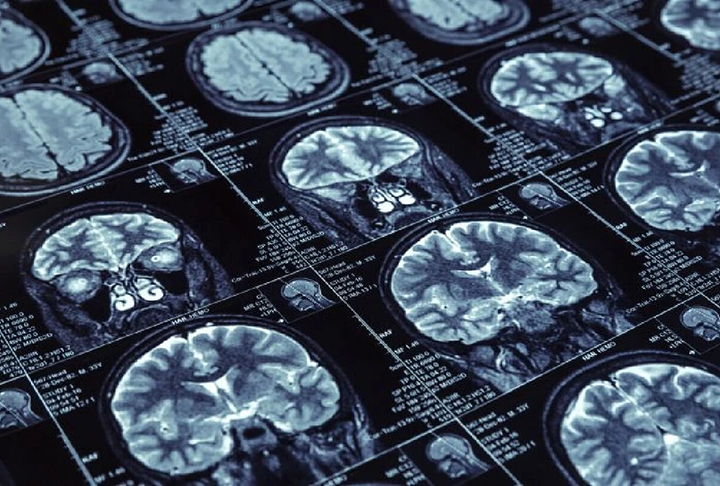

Mundo deve ter 139 milhões de pessoas com Alzheimer em 2050